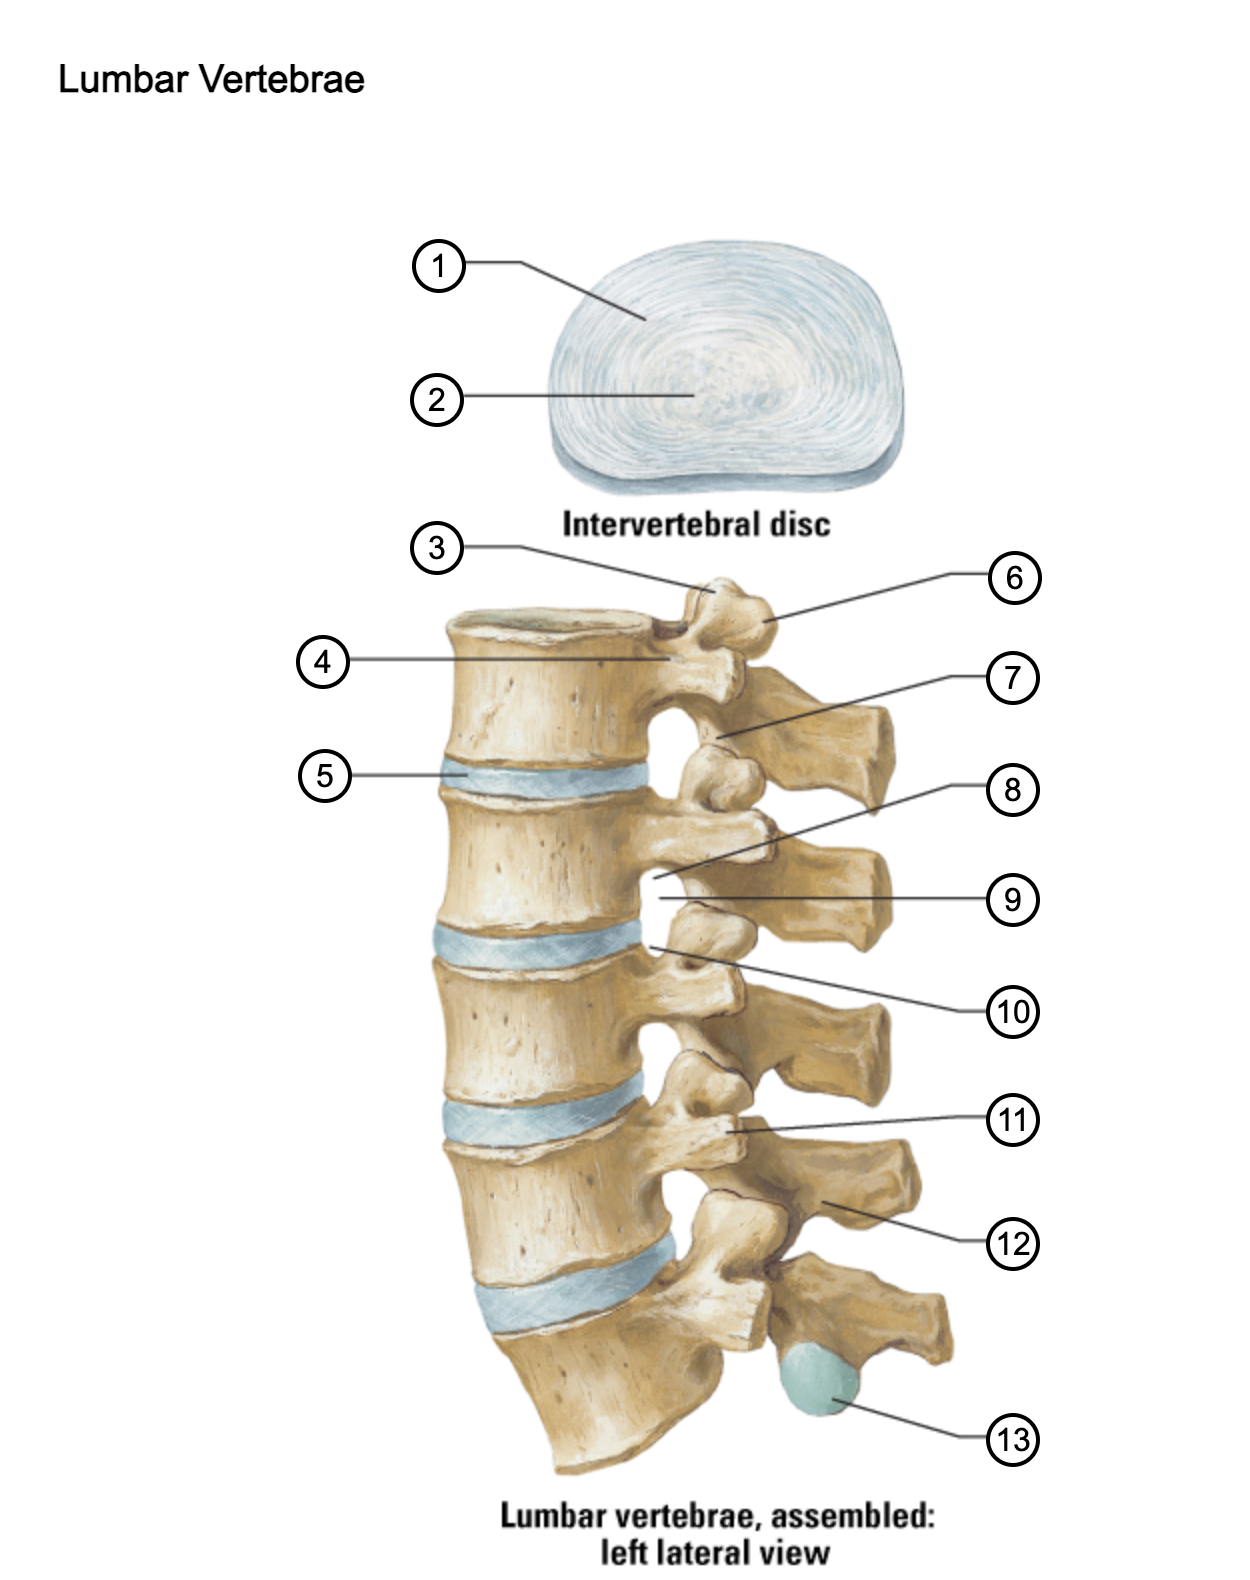

1

anulus fibrosus

2

nucleus pulposus

3

superior articular process

4

pedicle

5

intervertebral disc

6

mammillary process

7

inferior articular process

8

inferior vertebral notch

9

intervertebral notch

10

superior vertebral notch

11

transverse process

12

lamina

13

inferior articular facet